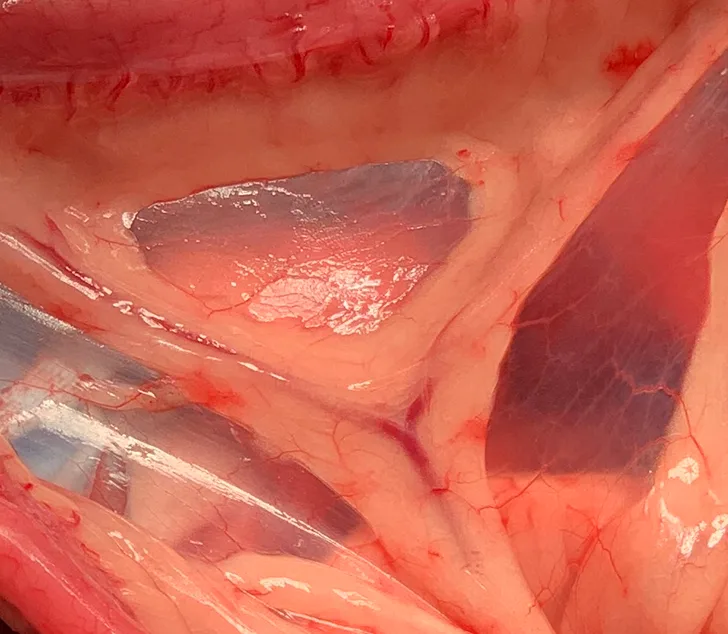

Treatment of intestinal intussusception involves laparotomy with manual reduction if the affected segment appears potentially viable and/or resection and anastomosis of the affected intestinal segment if neoplasia is the underlying cause or if the affected segment is necrotic or cannot be reduced (Figures 2-4).

FIGURE 2

A portion of intestine after intussusception reduction. There is serosal tearing (short arrow) and significant erythema (long arrow).